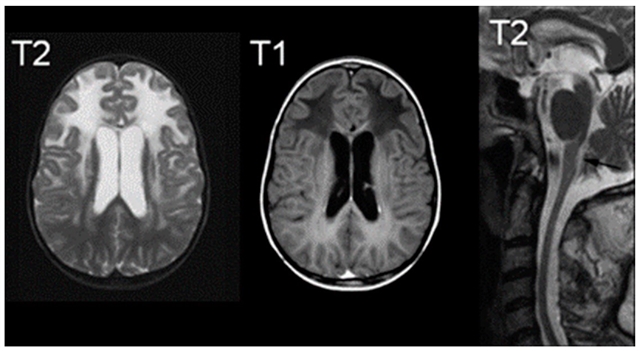

• MRI 诊断标准:满足广泛额叶白质异常、脑室周围边缘信号改变、基底节与丘脑受累、脑干异常、病灶强化 5 项中 4 项即可确诊。

亚历山大病典型的磁共振成像表现;右侧图像显示 T2 信号增高,中间图像显示 T1 信号减低,右侧图像为 T2 中线矢状位切面,可见萎缩征象